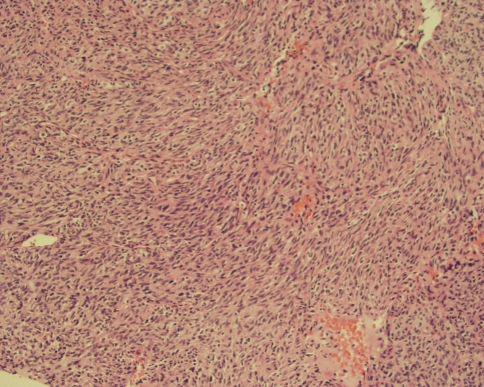

Fig. 5.

A low-power view shows a spindle cell tumor arranged in a herringbone-type pattern with focal areas of hemorrhage (Stain, hematoxylin and eosin; magnification, ×10).

The tumor was comprised of plump atypical spindle and ovoid cells arranged in a fascicular or herringbone-type pattern (Fig. 5). The cells appeared immature with minimal to mild eosinophilic fibrillary cytoplasm. There was minimal pleomorphism and frequent mitoses (10–11 per 5 high power fields.) The mass also contained scattered amounts of chronic mononuclear inflammatory cells (Fig. 6). Focal areas of hemorrhage and necrosis also were identified. Immunohistochemical staining for CD34, CD31, Factor VIII, HHF-35, SMA, desmin, S-100, and keratin were all negative. CD99 was positive. Ki-67 (proliferative index) was approximately 20% to 30%. FISH analysis for FKHR on 13q14, SYT on 18q11.2, and EWSR on 22q12 were negative. Reverse-transcription polymerase chain reaction (RT-PCR) was positive for ETV6/NTRK3 t(12;15)(q13;q25) translocation.

Microscopically, congenital fibrosarcoma is a hypercellular, hyperchromatic, anaplastic spindle cells tumor arranged in a herringbone pattern, with frequent mitoses, necrosis, and hemorrhage [4]. Immunohistochemistry and cytogenetics often are needed, and show negative staining for SMA, S-100, desmin, CD31, and CD34 [19]. Congenital fibrosarcoma is characterized by a recurrent t(12;15)(p13;q25) rearrangement, producing the ETV6 (TEL):NTRK3 (neurotrophin-3 receptor) fusion protein identified by RT-PCR [20, 34] and not expressed by the adult-type fibrosarcoma [33].